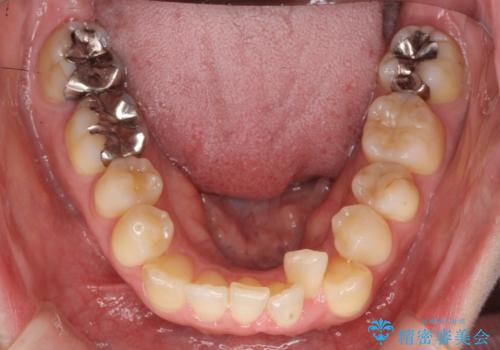

40代の矯正 八重歯を綺麗に

- 前歯のガタガタを主訴に来院。

・正中を顔にしっかり合わせるには、上下左右4本抜歯

・出来るだけ合わせる程度でよければ、左のみ上下2本抜歯。但し上下正中は揃わないかもしれない。

を提案し、

2本抜歯を選択されました。

矯正用のミニスクリューを使用し、また、前歯をIPRすることで正中の左へのずれを最小限に抑えています。